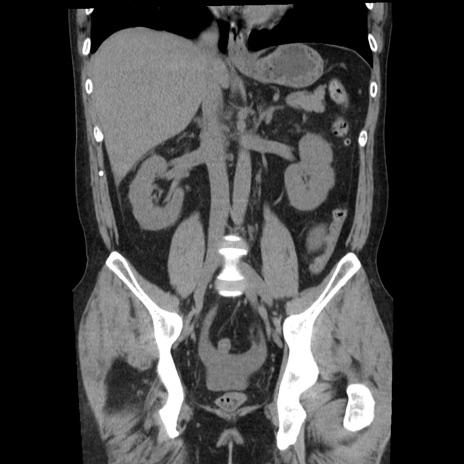

症例29(冠状断像)

【症例】40歳代男性

【現病歴】2日前から胃痛あり。徐々に周期的な激痛に変化した。本日になっても激痛があるため受診。

【身体所見】意識清明、BT 38-39℃台あり、腹部:膨満、やや硬、右下腹部に圧痛あり。

【データ】WBC 8500、CRP 23.26

横断像